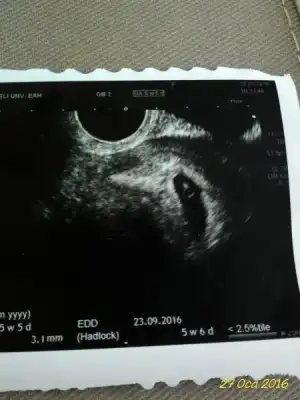

Iste benim mucizem

Eklentiler

• 20160128_141212.webp

20160128_141212.webp

21,3 KB · Görüntüleme: 226